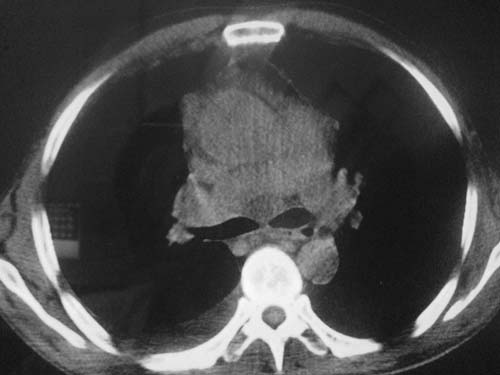

以下是引用科室第一人在2010-3-25 20:30:00的发言:[br]1:纵膈肿瘤性病变,恶性胸腺瘤可能性大伴纵膈右肺门淋巴结转移,右侧胸腔积液。[br]2:右侧肺门肿瘤性病变,纵膈淋巴结转移,右侧胸腔积液。右下叶转移。

以下是引用子期在2010-3-25 21:00:00的发言:[br]先考虑右中央型肺癌伴转移。

以下是引用江广1996在2010-3-25 22:49:00的发言:[br]通常肺癌向纵隔转移多见,纵隔肿瘤向肺内转移少见(有的表现为向肺内侵润)。本例以一元论考虑:右中心型肺癌并纵隔淋巴等多处转移。[br][br][本贴已被 江广1996 于 2010-3-25 22:50:07 修改过]

以下是引用yangyudong333在2010-3-26 6:43:00的发言:[br]“冰冻纵膈”,考虑纵膈淋巴瘤伴肺内及胸膜侵润。